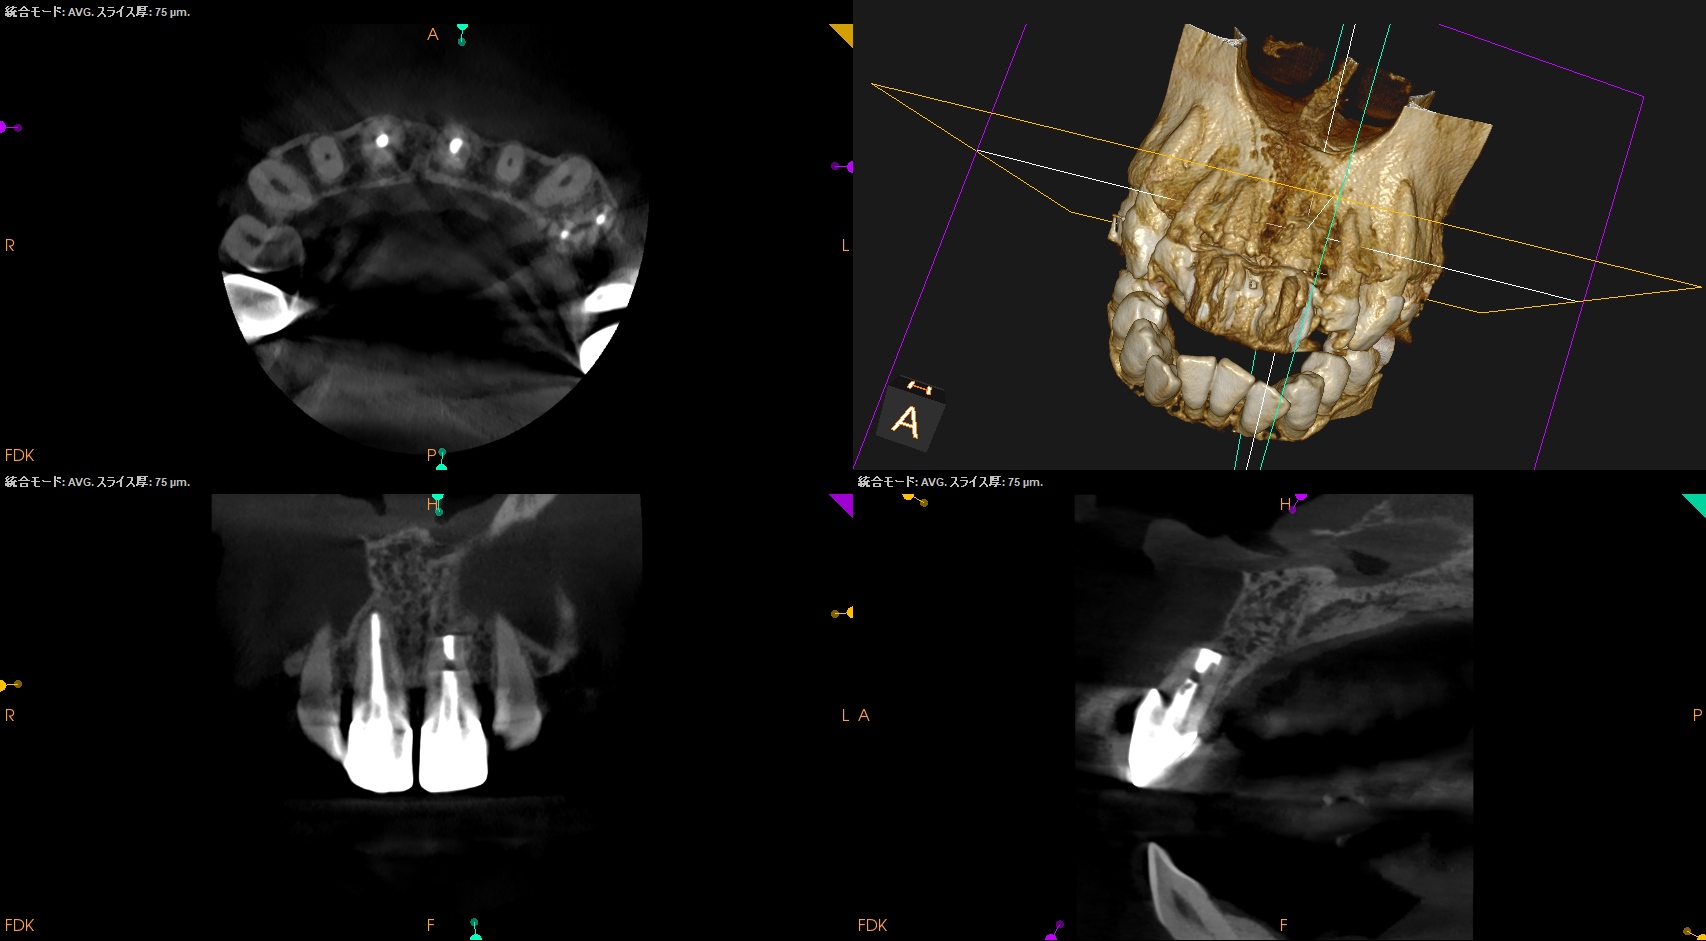

#9 Apicoectomy 2yr recall(2026.1.15)

臨床症状は消失したままで、最終補綴が装着されていた。

2年前の術直後は

歯槽骨はなかったが、再生した。